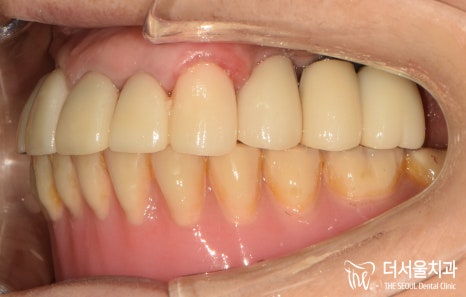

보내드리고 제작된 최종 보철을

체결한 사진입니다.

산성역치과에 처음 찾아오셨을 때와

다르게 많이 깔끔해졌습니다.